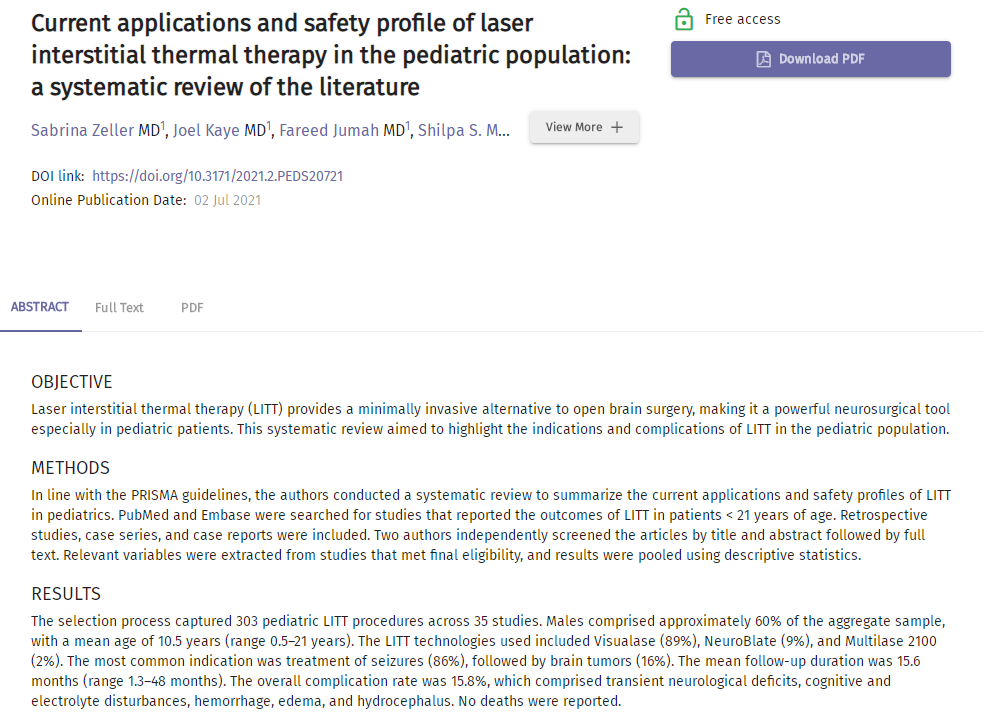

表1:儿童患者LITT的适应症和并发症报告部分截图

根据PRISMA指南,研究人员进行了系统的综述,总结了目前LITT在儿科的应用和安全概况。在PubMed和Embase中搜索报道小于21岁患者LITT治疗结果的相关研究。涵盖了35项研究中的303例儿童LITT手术。男性约占总体样本的60%,平均年龄为10.5岁(范围为0.5-21岁)。使用的LITT技术包括Visualase(89%)、NeuroBlate(9%)和Multilase 2100(2%)。最常见的适应症是治疗癫痫(86%),其次是脑瘤(16%)(见表1)。平均随访时间为15.6个月(1.3-48个月)。总的并发症发生率为15.8%,包括短暂的神经功能缺损、认知和电解质紊乱、出血、水肿和脑积水(见表2)。没有死亡报告。研究发现:到目前为止,LITT在儿科最常见的应用集中在治疗药物难治性癫痫和难以切除的脑肿瘤。LITT的安全性可以为儿科人群提供一种有吸引力的脑外科手术替代方案。